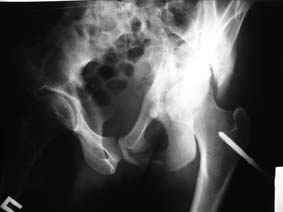

Re: Повреждение вертлужной впадины 2,5 мес.

Это обзорные и косые снимки